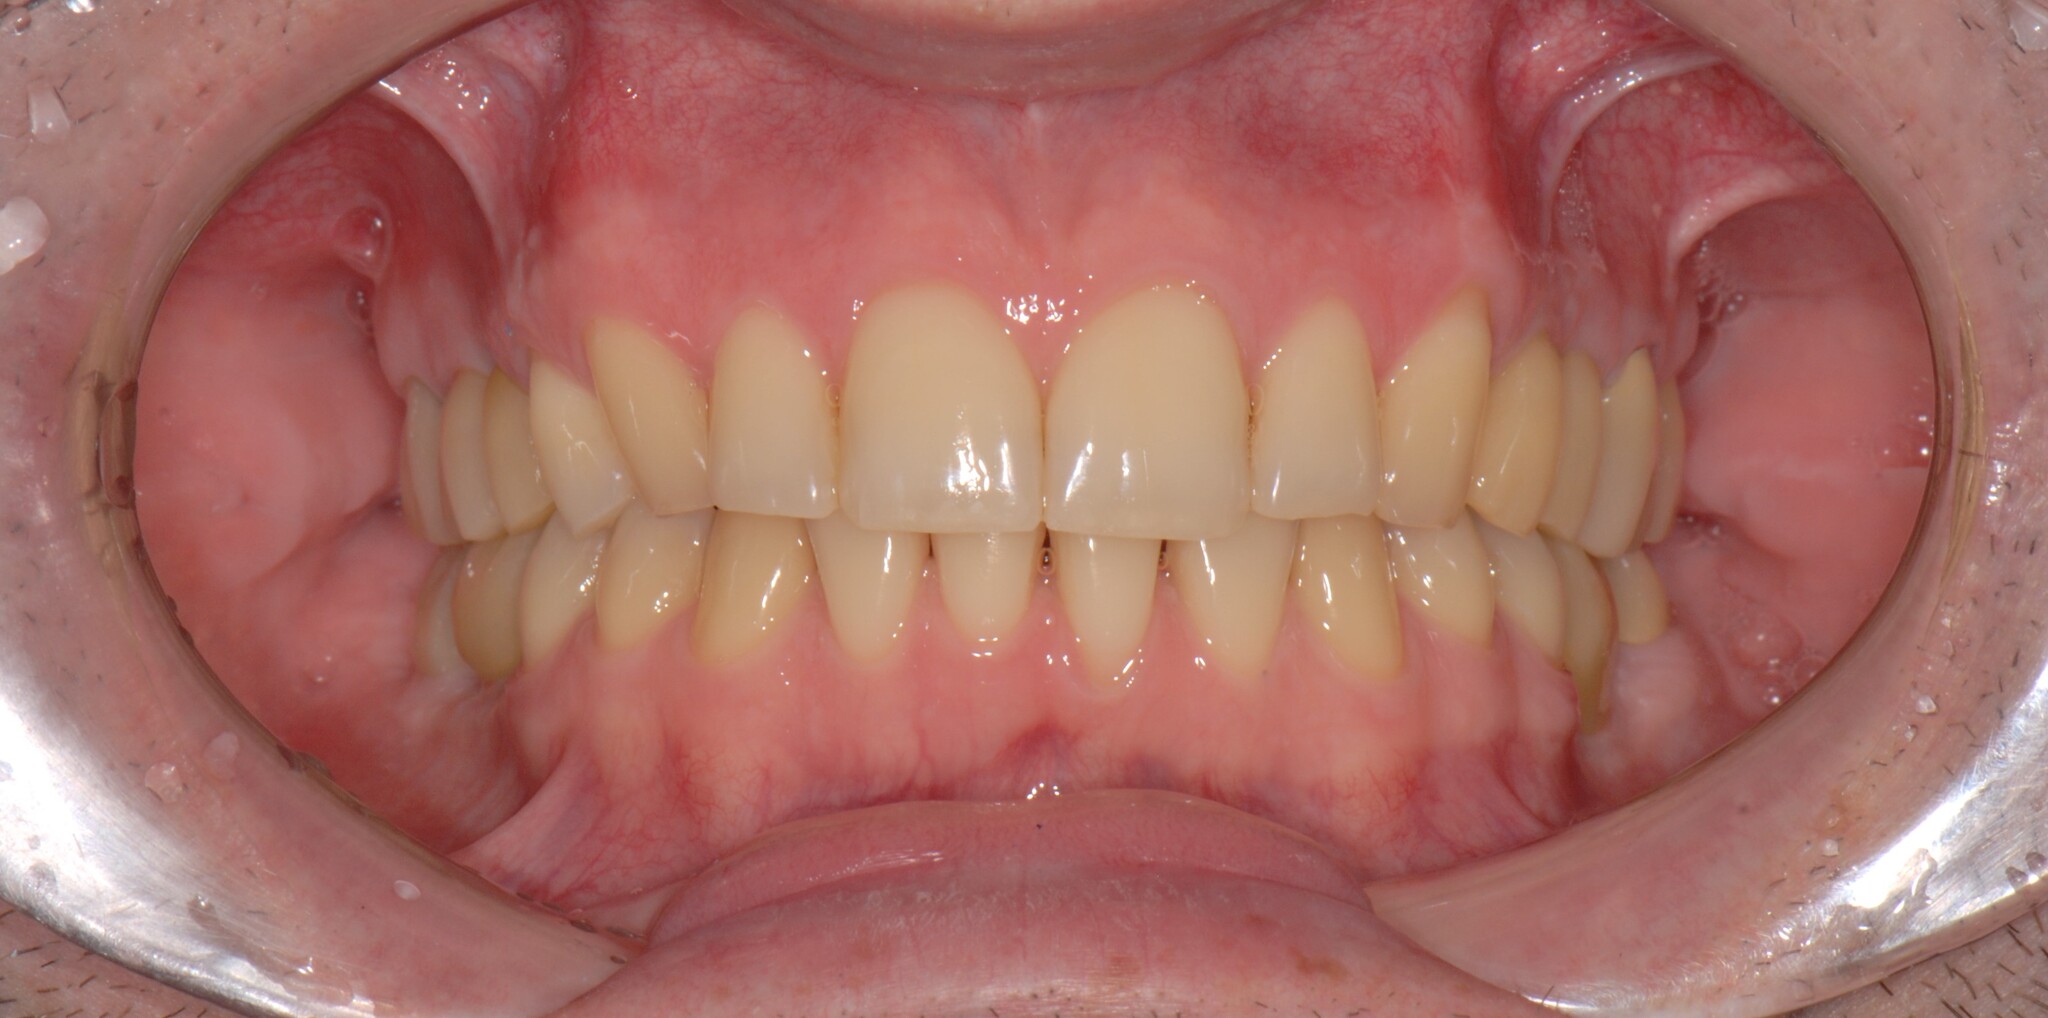

Стало: